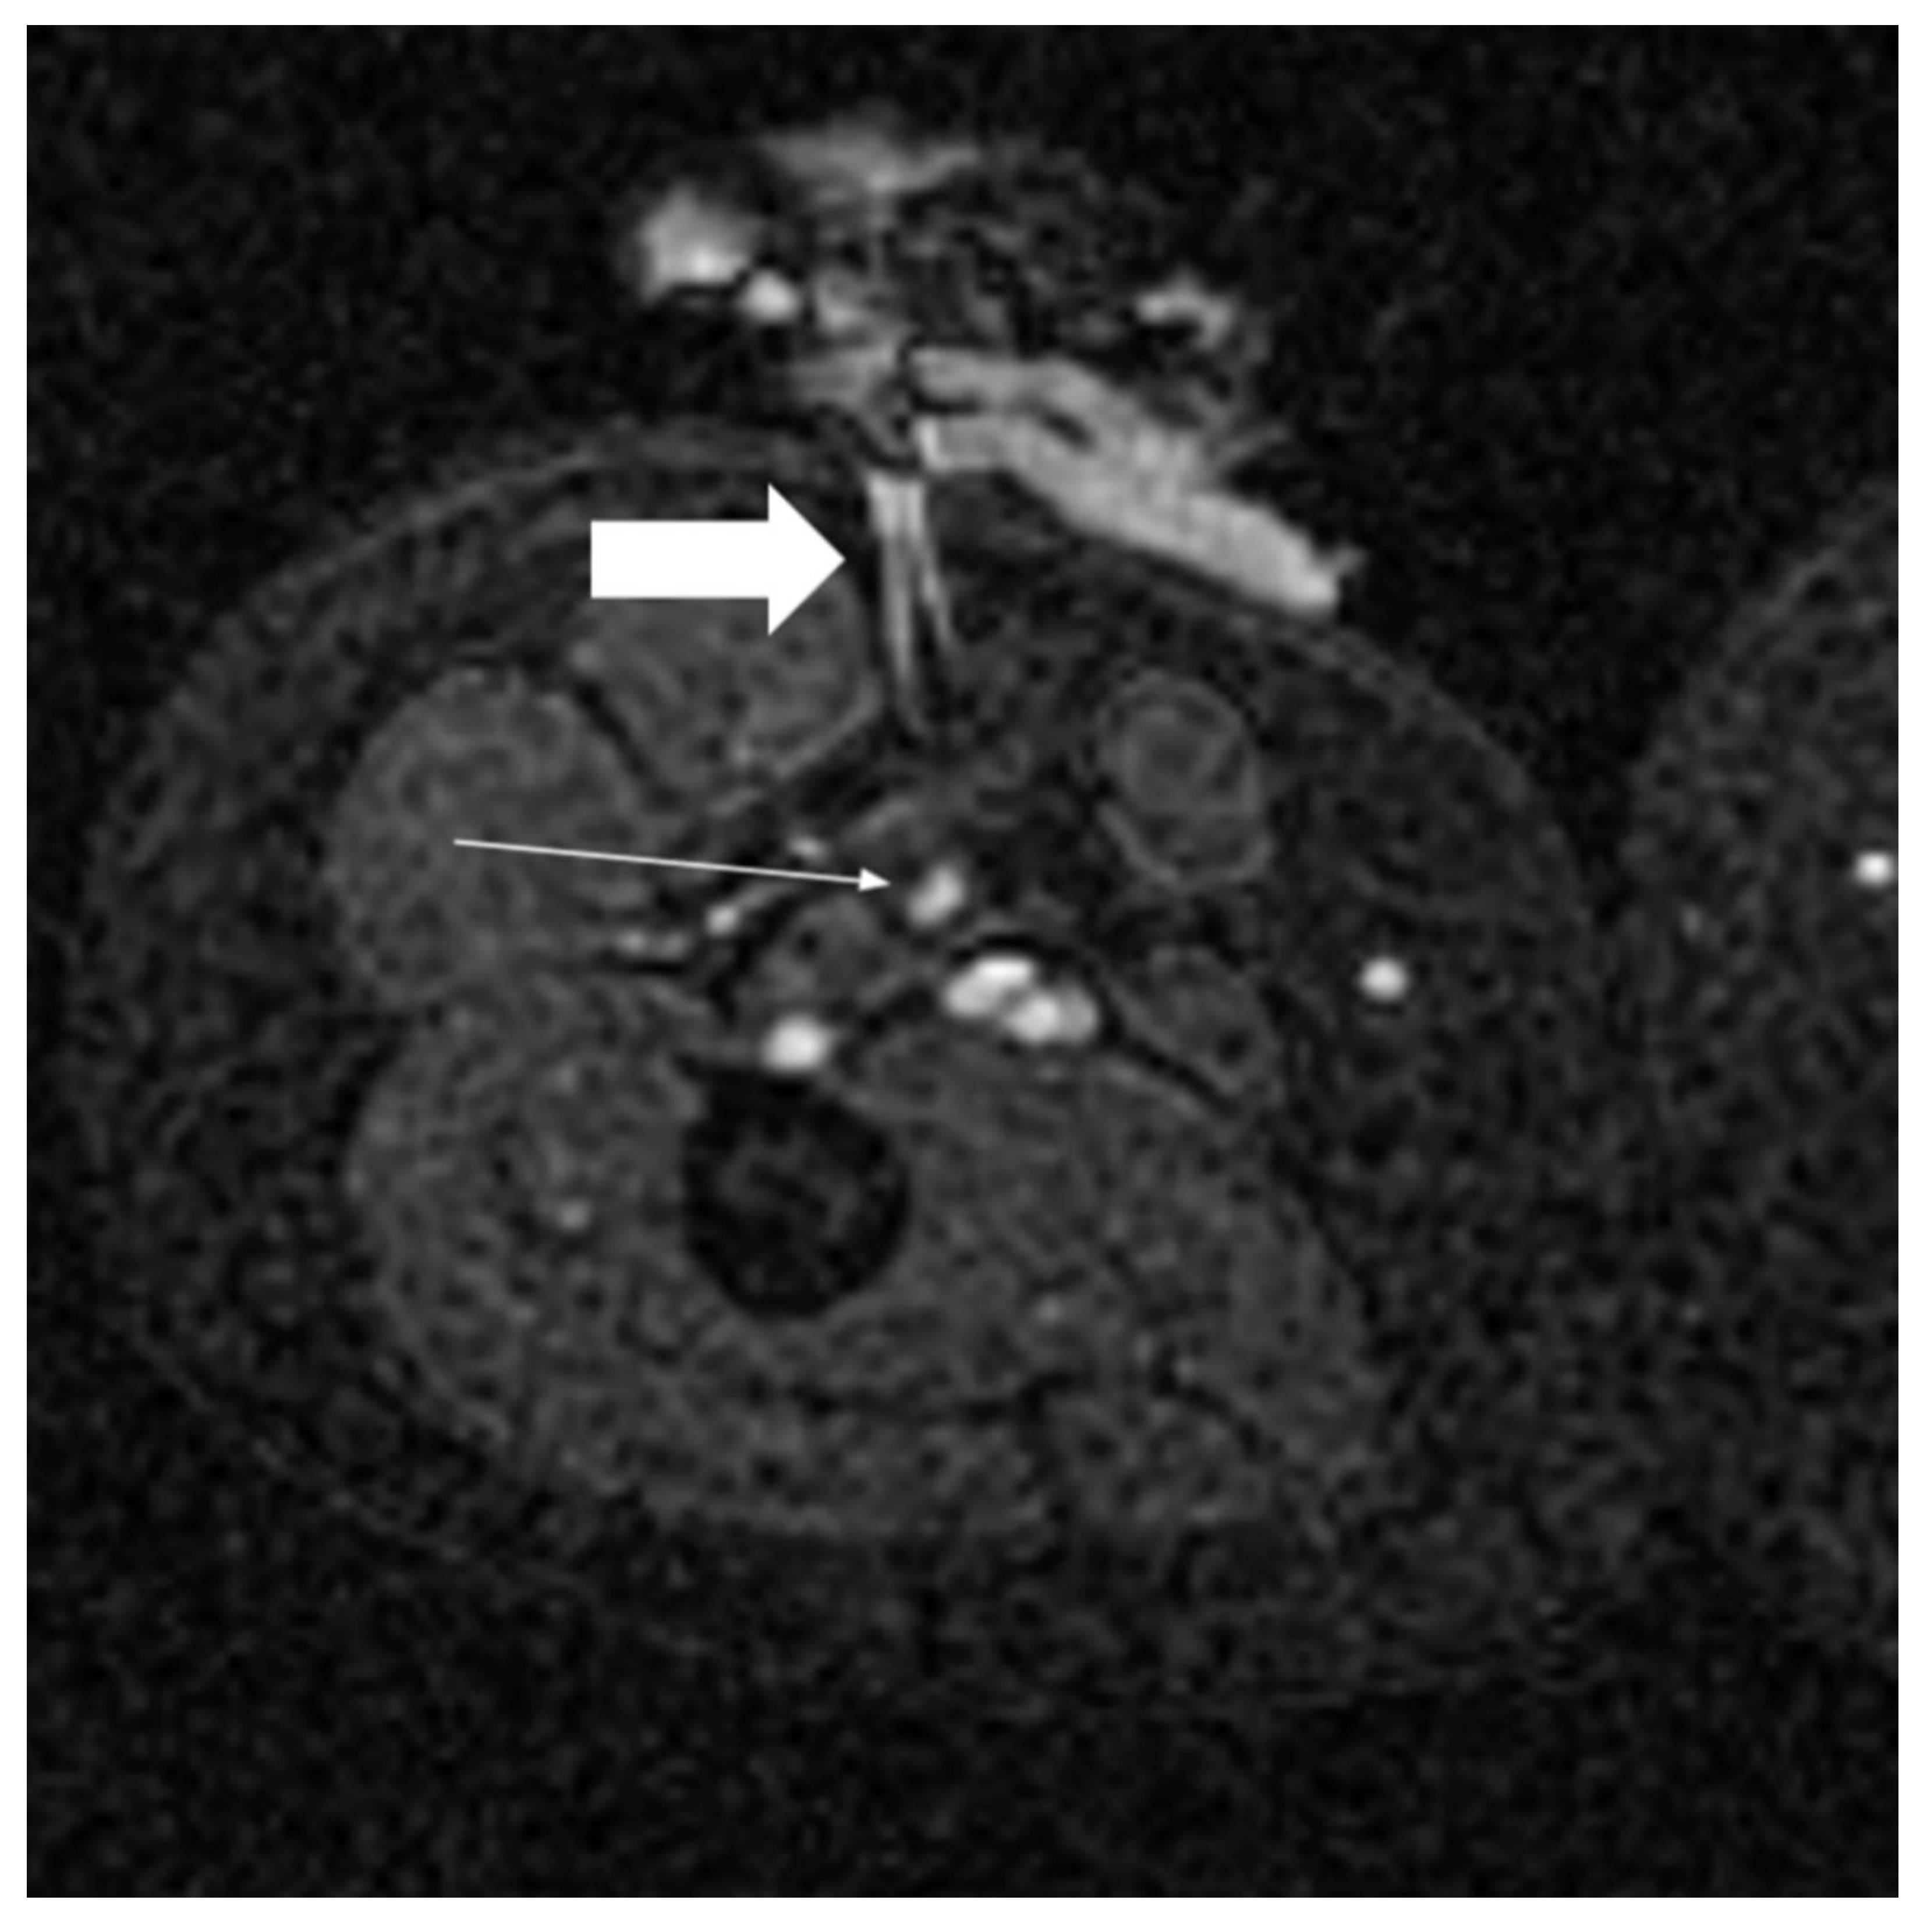

- De Marini, P.; Cazzato, R.L.; Garnon, J.; Shaygi, B.; Koch, G.; Auloge, P.; Tricard, T.; Lang, H.; Gangi, A. Percutaneous MR-Guided Prostate Cancer Cryoablation Technical Updates and Literature Review. BJR Open 2019, 1, 20180043. [Google Scholar] [CrossRef] [PubMed]

- De Marini, P.; Cazzato, R.L.; Garnon, J.; Dalili, D.; Leonard-Lorant, I.; Leclerc, L.; Autrusseau, P.-A.; Auloge, P.; Weiss, J.; Tricard, T.; et al. Safety and Oncologic Efficacy of Percutaneous MRI-Guided Cryoablation of Intraparenchymal Renal Cancers. Diagn. Interv. Imaging 2021, 102, 531–538. [Google Scholar] [CrossRef]

- Cazzato, R.L.; De Marini, P.; Auloge, P.; Leclerc, L.; Tricard, T.; Linder, V.; Jost, M.; Ramamurthy, N.; Lang, H.; Garnon, J.; et al. Diagnostic Accuracy and Safety of Percutaneous MRI-Guided Biopsy of Solid Renal Masses: Single-Center Results after 4.5 Years. Eur. Radiol. 2021, 31, 580–590. [Google Scholar] [CrossRef]